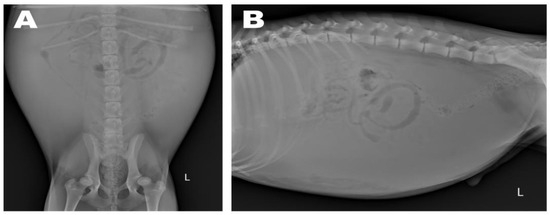

Abdominal radiographs showed severe abdominal distention and a loss of serosal detail (Figure 1); no significant findings were observed apart from these. Transthoracic echocardiography showed an echo-dense, band-like structure within the right atrial chamber, extending from the atrioventricular junction to the free atrial wall (Figure 2A). The right atrium was divided into cranial and caudal chambers. Color Doppler imaging revealed continuous venous blood inflow from the caudal chamber to the cranial chamber through a perforation in the remnant membrane, confirming an abnormal venous blood inflow in the right atrium. An agitated saline study was performed using 3 mL of normal saline to further characterize the flow in the right atrium. Microbubbles were made with saline solution, two syringes, and a three-way stopcock. These were injected in the left cephalic vein and the contrast was noted only in the right atrial cranial chamber and the right ventricle immediately afterward (Figure 2B). When the microbubbles were injected in the left lateral saphenous vein, these reached immediately the right atrial caudal chamber; and some moved into the cranial chamber through a perforated membrane (Figure 2C). This confirmed the presence of a cranial true chamber (CrTC) and cranial vena cava (CrVC) as well as a caudal accessory chamber (CdAC) and caudal vena cava (CdVC). A thoracic computed tomography scan was performed using 30 mL of iohexol contrast agent (Omnipaque, GE Healthcare China). Strong contrast enhancement was observed in the cranial chamber that communicated with the CrVC (Figure 3) during the dextrophase (25 s after contrast injection); in contrast, weak contrast enhancement was observed in the caudal chamber connected to the CdVC. A venous blood inflow obstruction was observed in the right atrium connected to the CdVC, suspected of causing severe ascites. Based on these imaging findings, the patient was diagnosed with CTD, and surgical correction was advised. Both interventional procedures and open-heart surgery can be options for treating CTD. However, considering the potential risk of re-stenosis following interventional treatment, a curative resection involving surgical membranectomy via VIO was planned.

Figure 3. Preoperative computed tomography in the dextrophase: dorsal plane (A) and sagittal plane (B). While the caudal accessory chamber (CdAC) communicating with the caudal vena cava (CdVC) exhibited no contrast enhancement, the cranial true chamber (CrTC) communicating with the cranial vena cava (CrVC) showed pronounced contrast enhancement. The septum-like structure distinctly divided the right atrium into two distinct sections.